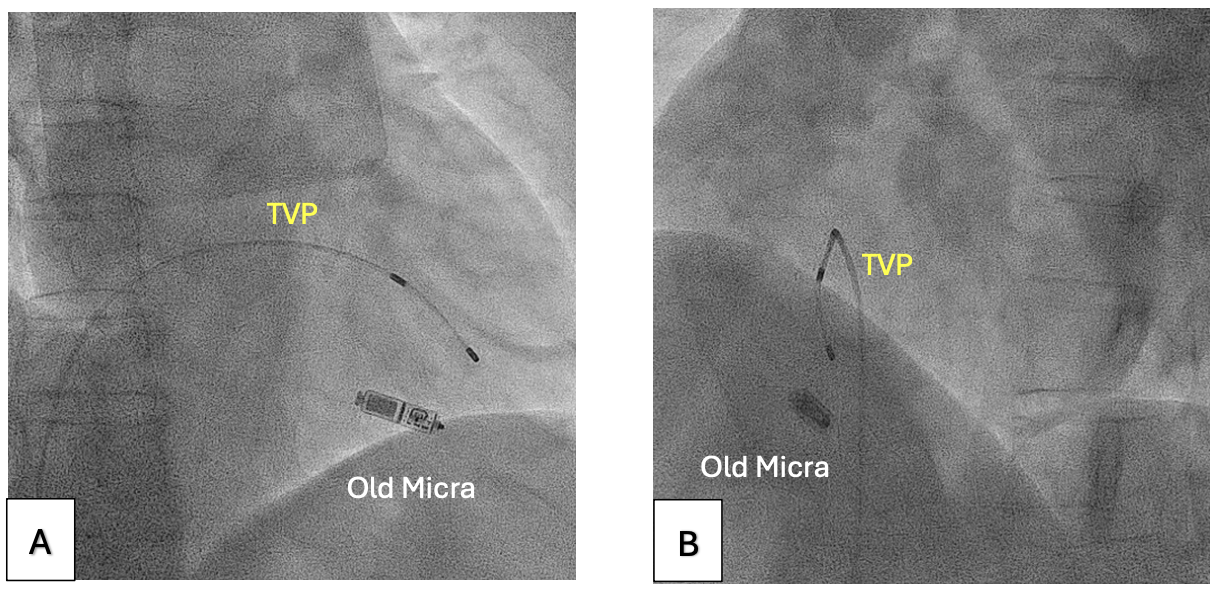

Right ventriculography was performed via right femoral venous access to outline the right ventricular (RV) septum (Figure 1, Video 1). A 5F Arrow temporary venous pacing (TVP) catheter (Teleflex) was then used to measure the pacing thresholds at multiple sites along the RV septum. The site with the lowest threshold was identified and fluoroscopically roadmapped in right and left anterior oblique (LAO) views to guide deployment (Figure 2, Video 2). The venous sheath was exchanged for the 23F Micra delivery sheath, and the new Micra AV was successfully deployed at the pre-identified site (Figure 3, Video 3), achieving a pacing threshold of 0.5V at 0.24 milliseconds and an estimated battery longevity of greater than 10 years.

TVP enables rapid testing of pacing thresholds at various sites, allowing identification of the site with the lowest threshold before Micra deployment. Although no contrast is used to mark the TVP tip position, its relationship to surrounding anatomical landmarks (eg, ribs, vertebrae) can be noted under consistent fluoroscopic angles and table height. Maintaining these imaging parameters during Micra deployment ensures accurate targeting of the optimal site. This method is also applicable when the pacing threshold remains suboptimal after multiple Micra deployment attempts. In such cases, a large-bore sheath (eg, 16F) can be inserted into the 23F Micra delivery sheath to prevent back-bleeding. A 5F or 6F sheath is then inserted into the 16F sheath, enabling insertion of the TVP catheter to map and identify an optimal pacing site.